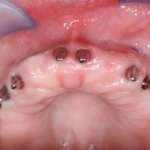

Riabilitazione di un’arcata superiore completa in una situazione di edentulia totale

Il case report presenta un intervento riabilitativo di un mascellare superiore con il concetto Neoss4+: un ponte fisso supportato da 4 impianti Neoss ProActive Edge. Il trattamento pianificato ha consentito il posizionamento degli impianti senza innesto osseo